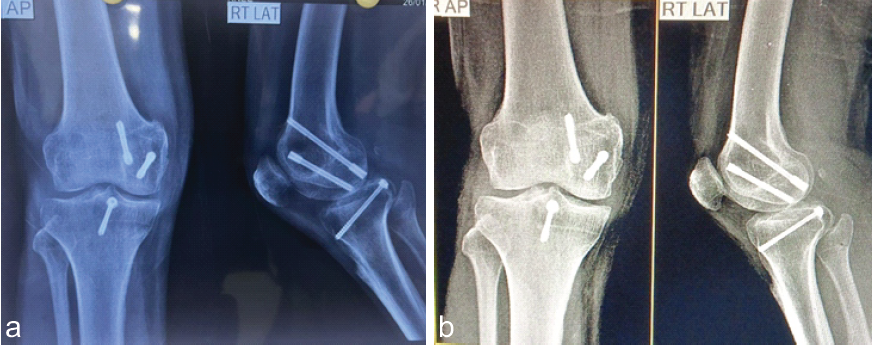

Postoperatively, the patient was immobilized in a knee brace for the initial period to allow for adequate healing of the fracture and PCL fixation. Early passive range of motion exercises were initiated after 2 weeks, followed by a gradual progression to active range of motion and strengthening exercises. The patient was non-weight-bearing for the first 6 weeks and then transitioned to partial weight-bearing as tolerated. The patient was followed up at regular intervals postoperatively. At 6 months, the patient demonstrated excellent functional outcomes. He achieved a knee range of motion from 0 to 130° with no significant pain or instability (Fig. 5a, b, c). Radiographs confirmed satisfactory fracture union (Fig. 6a and b).

Figure 6: (a and b) Radiographic follow-up at 6 months and 18 months showing healed fracture.

Functional assessment using the knee injury and osteoarthritis outcome score and the Lysholm knee scoring scale revealed high scores, indicating excellent knee function and patient satisfaction. The patient was further followed up for 18 months, revealing no functional deficit or pain.